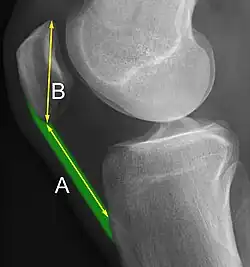

The Insall-Salvati ratio helps to indicate patella baja on lateral X-rays, and is calculated as the patellar tendon length divided by the patellar bone length. An Insall-Salvati ratio of < 0.8 indicates patella baja.[7]

- ^ a b Douglas Dennis (2017-02-25). "TKA in Patella Baja (Infera)". Orthobullets. Retrieved 2019-02-08.